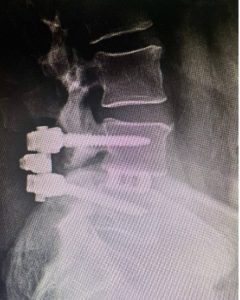

The third image is the postoperative X-ray taken six weeks after the L4 and L5 laminectomy and Transforaminal Lumbar Interbody Fusion (TLIF) back surgery.

In doing the TLIF spinal fusion, the surgeon stabilized the spinal vertebra. The result? It resolved all of the patient’s symptoms including his back pain and leg pain.